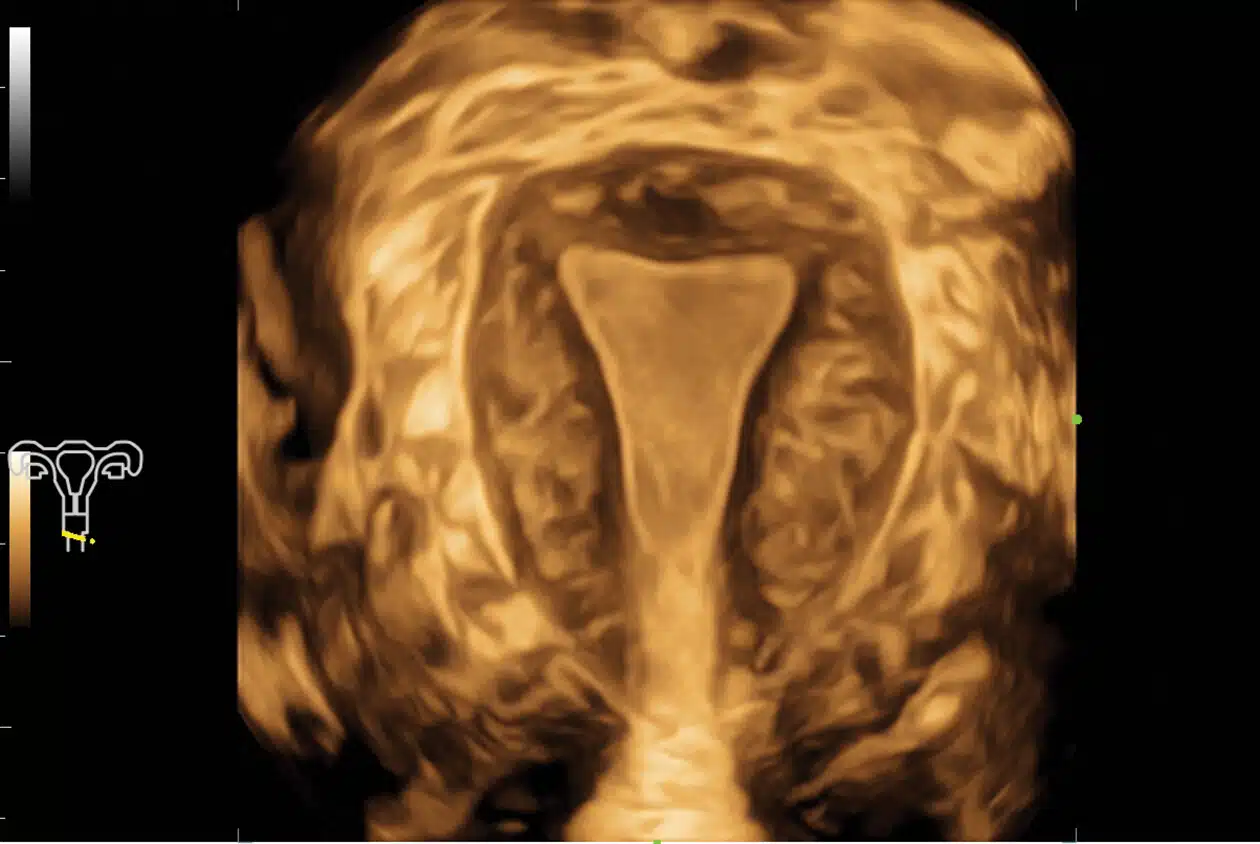

• Smart-Pelvic_Imagyn-I9.jpg-1

Smart Pelvic

Pelvic Floor Measurements

Enables users to quickly obtain 2D/3D automated GYN measurements of the pelvic floor by setting up a baseline and tracing the border of Levator Hiatus automatically.